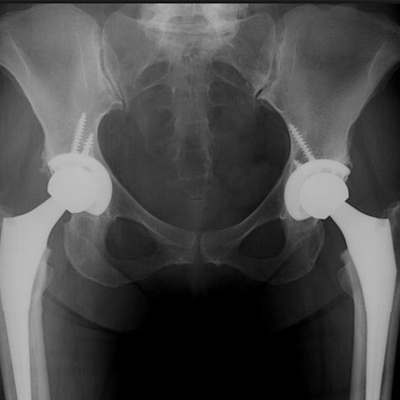

Bilateral Total Hip Replacement